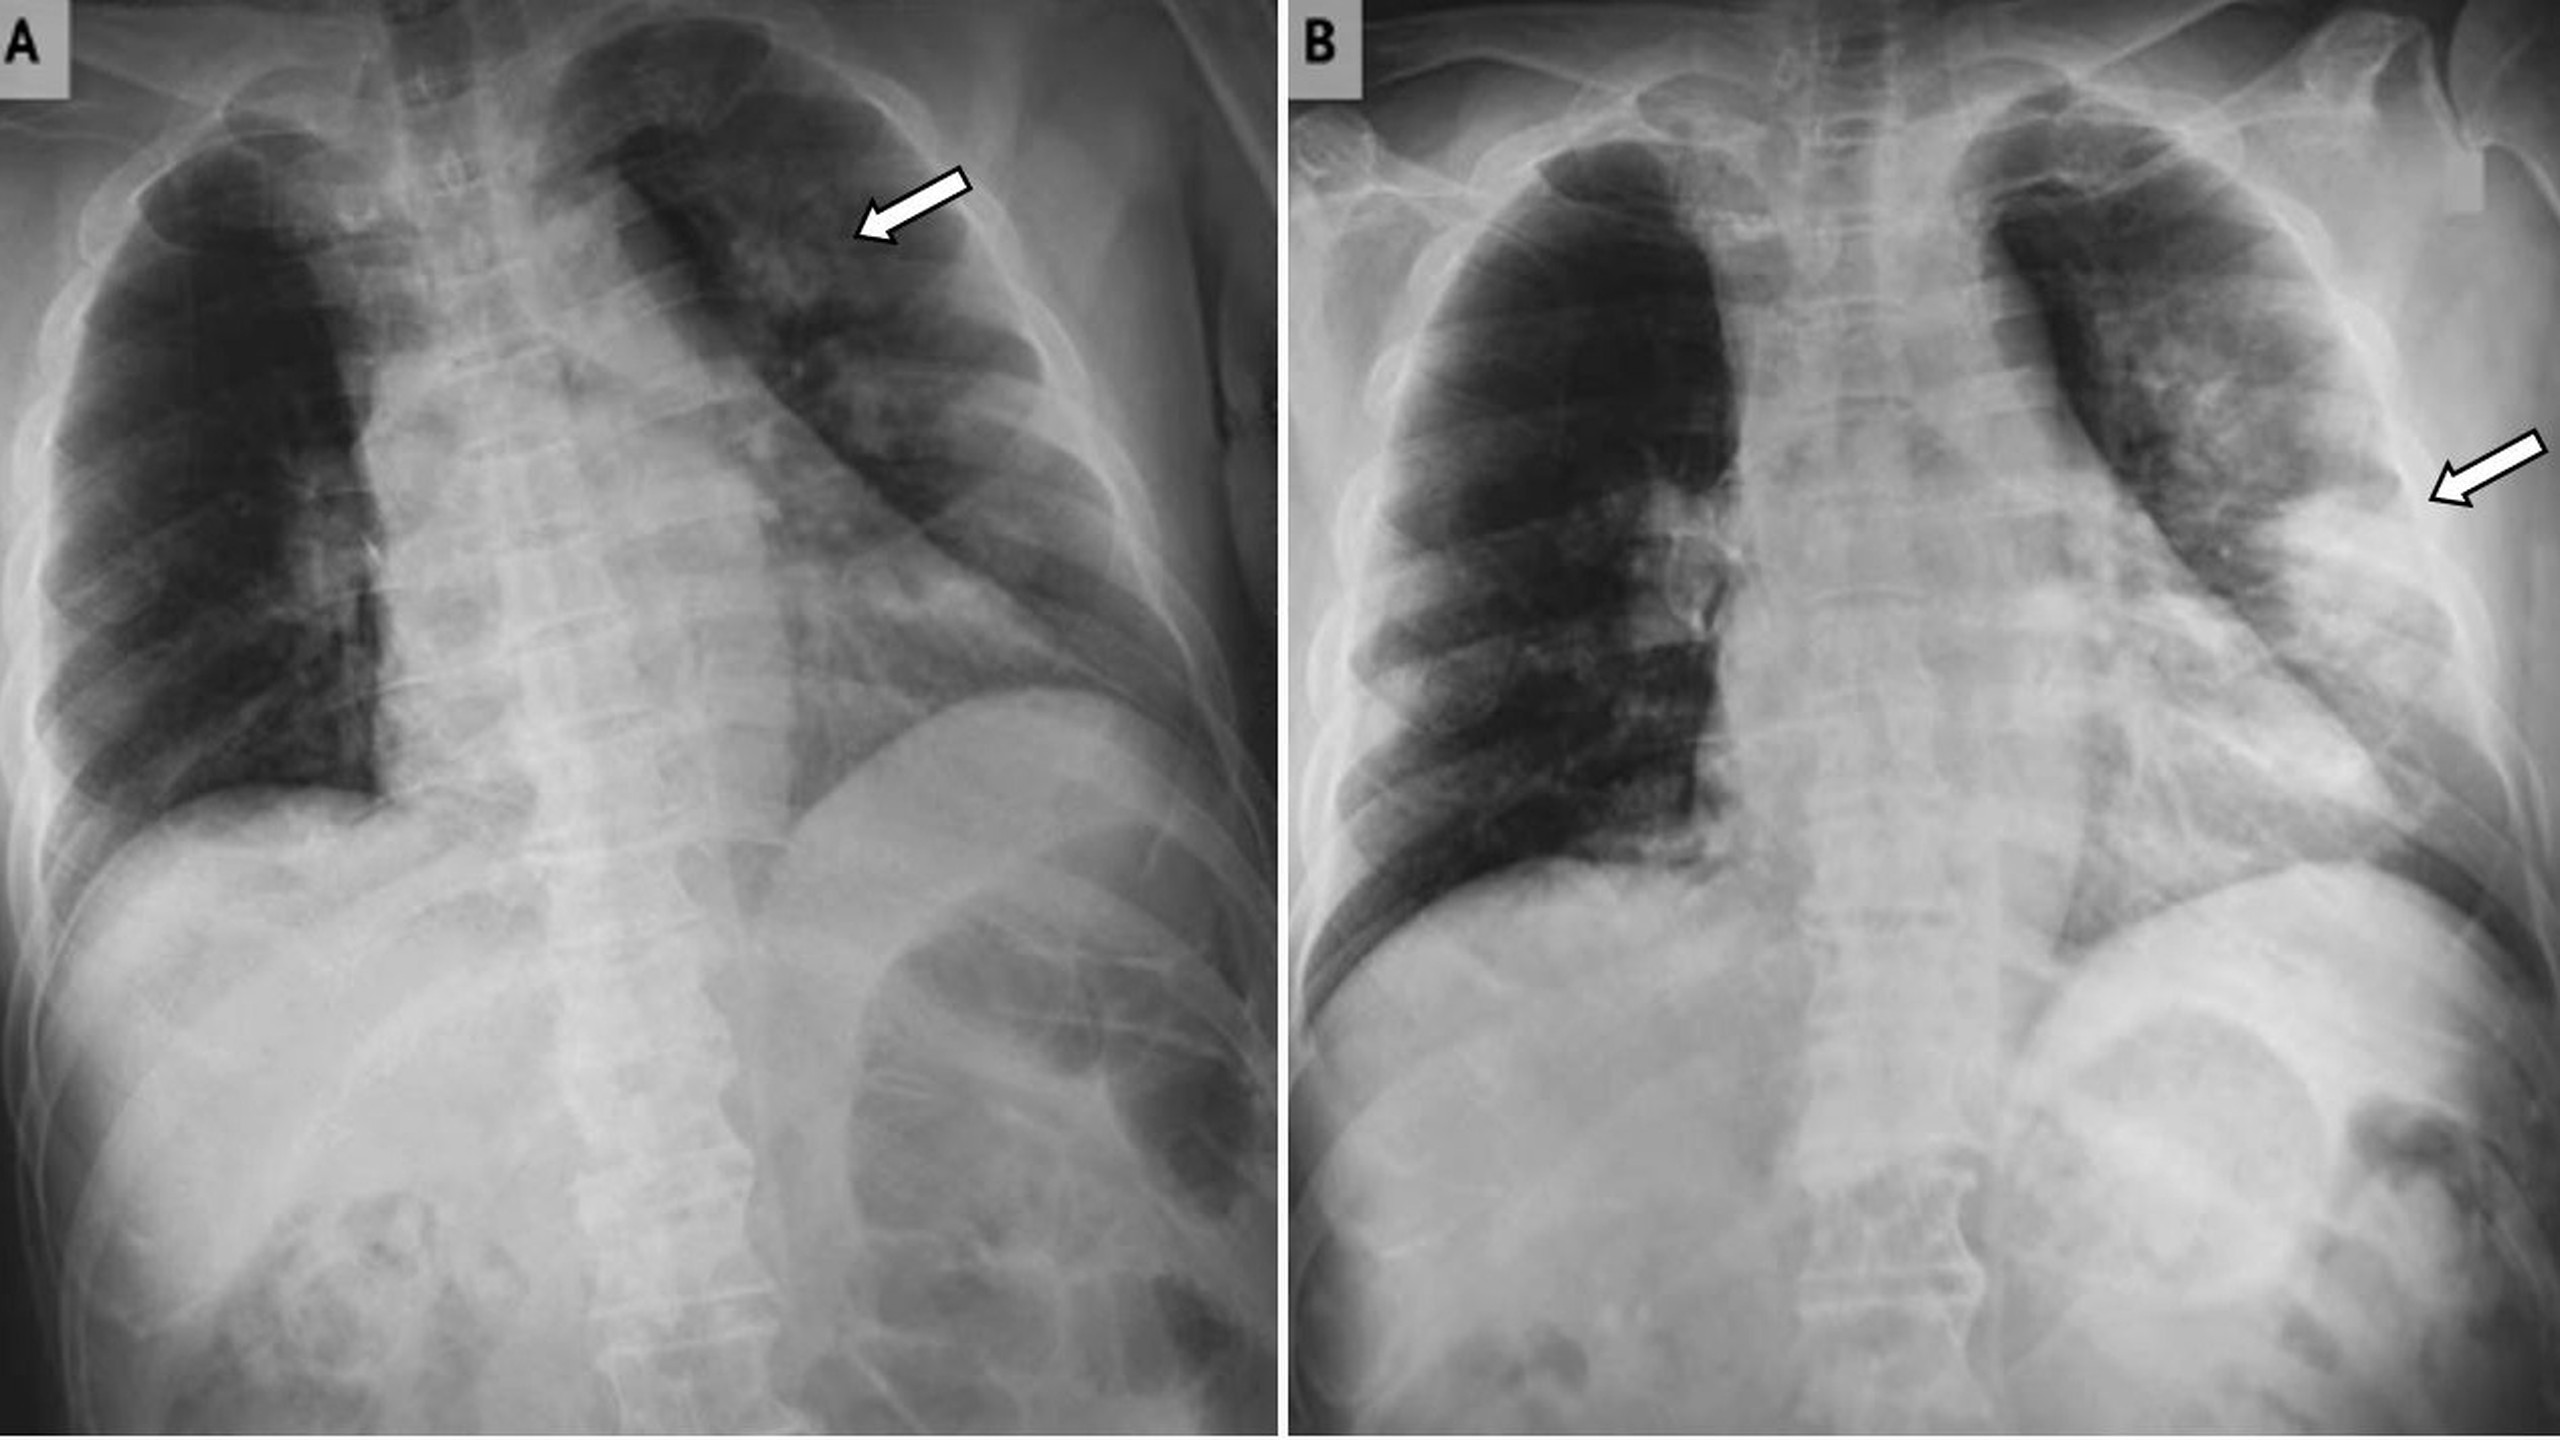

Nhồi máu phổi là do sự tắc nghẽn ở mạch máu phổi. Điều này sau đó dẫn đến thiếu máu cục bộ và có thể xuất huyết hoặc hoại tử mô của mô phổi. Nhồi máu phổi là bệnh lý tuy hiếm gặp nhưng rất nguy hiểm, cần chẩn đoán sớm và điều trị kịp thời để không ảnh hưởng đến tính mạng.

Nhồi máu phổi là do sự tắc nghẽn ở mạch máu phổi. Điều này sau đó dẫn đến thiếu máu cục bộ và có thể xuất huyết hoặc hoại tử mô phổi. Trong hầu hết các trường hợp, nguyên nhân dẫn đến nhồi máu phổi thường là do thuyên tắc phổi.

Các triệu chứng của nhồi máu phổi có thể thay đổi liên quan đến kích thước của nhồi máu và vị trí của nhồi máu trong phổi. Nhồi máu phổi lớn hơn thường gây ra các triệu chứng nghiêm trọng hơn, cũng nhồi máu ảnh hưởng đến màng phổi (màng xơ bảo vệ và bao phủ phổi).